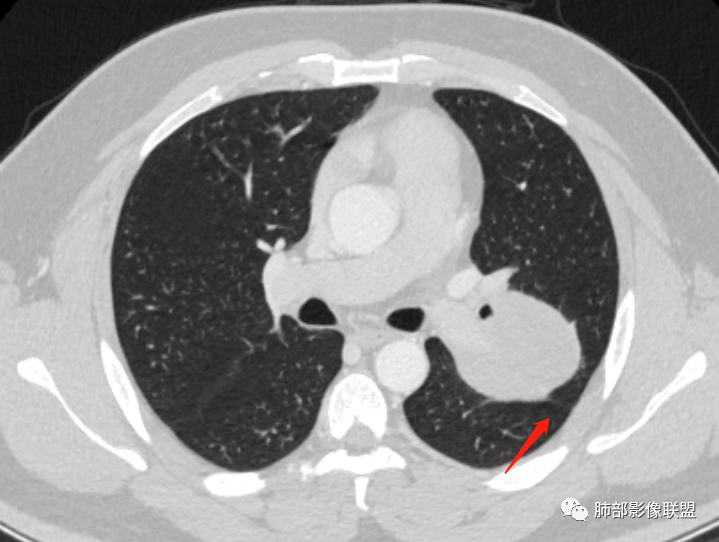

空气新月征:

新月征很有特点,血管有特点

蛇纹血管像sft,空气新月征像psp

青年男性,体检发现左肺不规则类圆形占位性病变,叶间裂区域,定位胸膜来源。左肺下叶支气管受压狭窄,但管壁光整,未见腔内阻塞或管壁受侵。包块边界清晰,浅分叶,内部密度不均匀,病灶后份见空气新月征。渐进性强化,增强动脉期见分支状血管,蛇纹血管征。肺门纵膈未见增大淋巴结,符合孤立性纤维瘤(SFT)。